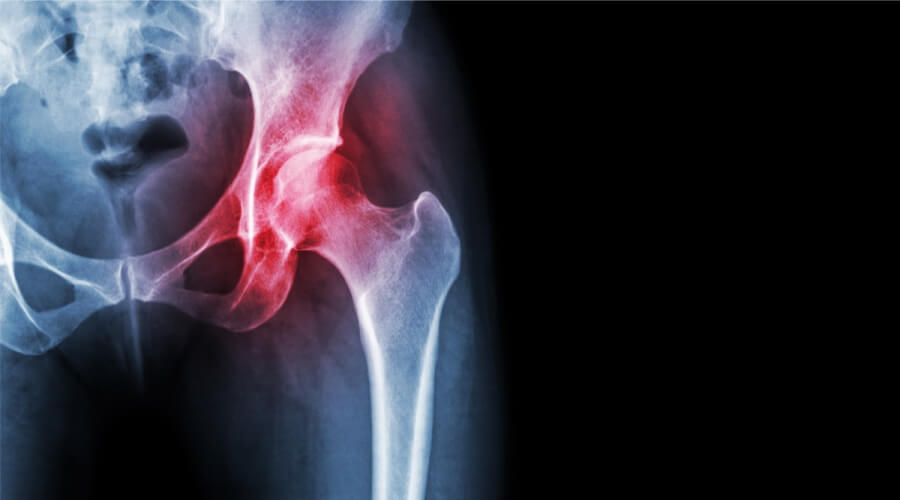

علاج آلام الورك الأيسر.. أعرف أسبابه وكيفية إدارته

يبحث الكثيرون عن علاج آلام الورك الأيسر، إذ يعتبر ألم الورك الأيسر مشكلة شائعة لدى الكثيرين، ولا ينبغي تجاهله، خاصةً إذا استمر الألم، فقد يشير إلى مشكلة صحية خطيرة تتطلب عناية فورية، ولذلك نوضح لكم أسباب آلام الورك الأيسر وأعراضه وطرق علاجه.

قبل التطرق إلى علاج آلام الورك الأيسر، يجب توضيح أسباب آلام الورك الأيسر، والتي تنشأ نتيجة عوامل مختلفة، تتراوح بين الحالات الخفيفة والخطيرة كالتالي: